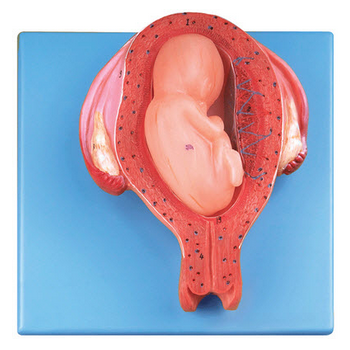

GD/A42005/6六個月胎兒模型產品介紹:1、尺寸:自然大,高14.5cm,寬16cm,厚6.5cm,共有14個部位指示標志。2、材質:進口PVC材料、進口油漆、電腦配色、高級彩繪有關GD/A42...